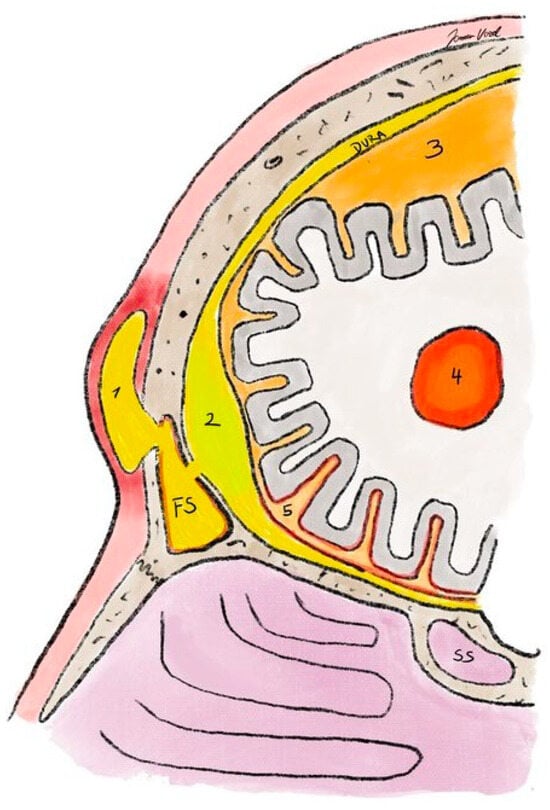

Figure 10. Illustration of cranial (i.e., bony) and intracranial complications or sinusitis. FS—frontal sinus; SS—sphenoid sinus; 1—Pott’s puffy tumor; 2—epidural abscess; 3—subdural empyema; 4—intraparenchymal abscess; 5—meningitis.

10. Intracranial Complications

If infection from the paranasal sinuses progresses intracranially, we refer to intracranial infection or complication (Figure 10). The spread occurs due to the close proximity of the paranasal sinuses to the intracranial space and due to venous drainage of the paranasal sinuses into the cerebral venous sinuses []. In most cases, symptoms are non-specific with headache and fever in addition to the clinical picture of sinusitis [].